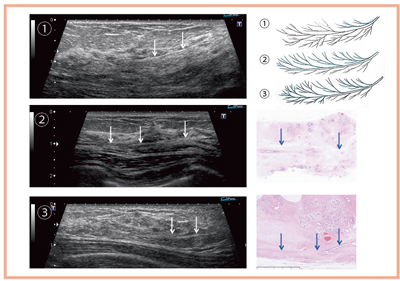

図14〜16は,経過観察としてよい病変と精査が必要な病変の,超音波画像と模式図である。等エコーな腫瘤性病変においても非腫瘤性病変と同様に,一斉に同じような流れで変化しているものは正常だが,がんの場合は逸脱し,パターンが乱れている。ただし,静止画で判別することは困難であり,リアルタイムで立体的に判断する必要がある。また,図15,16のようなパターンの乱れを見つけるためには,ある程度のグレースケールの分解能が必要となる。

![]() 図14 超音波の縞模様から精査の必要性を判断するポイント |

![]() 図15 等エコーな腫瘤性病変において精査の必要性を判断するポイント |